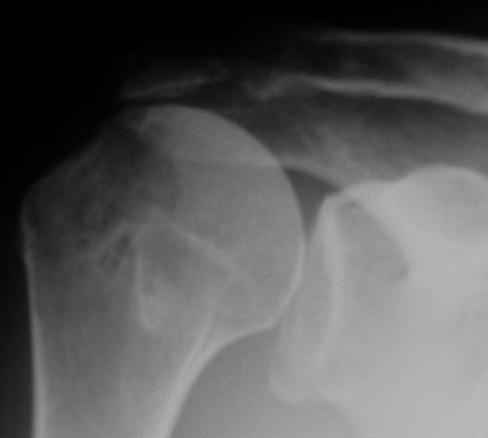

Верхний подвывих в такой ситуации может быть проявлением ротаторной артропатии, как следствия более массивного, чем частичный разрыв сухожилия надостной мыщцы, повреждения вращательной манжеты. И значит нужно думать о том, насколько полно восстановлена манжета, адекватно ли был расценен объем ее повреждения. Что за шов применялся? Якорных винтов не видно. И почему гипсовая иммобилизация? Есть прекрасные надувные отводящие подушки, позволяющие ранние движения.

В качестве примера - снимки до и после восстановления целостности вращательной манжеты после 3-хмесячной давности полного разрыва. Видно, что верхний подвывих устранен.

К сожалению, более подробной информации из выписного эпикриза почерпнуть не удалось (больной был оперирован, наблюдался и проходил реабилитацию в другом лечебном учреждении. Полностью согласен, что высокое стояние головки плеча, вероятнее всего, свидетельствует о неадекватном восстановлении ротаторной манжеты, к счастью пока без выраженных рентгенпризнаков ротаторной артропатии.